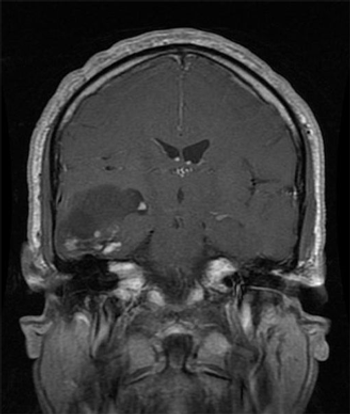

Conventional methods for treating brain metastasis, such as surgery, WBRT, and SRS, each compete with and complement one another. A plethora of recent studies have helped define and expand the utility of these tools.

It is time to put aside the pessimism of the past when it comes to brain metastases and embrace the wide array of clinical investigational opportunities arising in this field.

Some targeted systemic therapies have demonstrated evidence of activity in the brain-specifically in melanoma, lung cancers, and breast cancers-and these agents warrant further study in clinical trials.